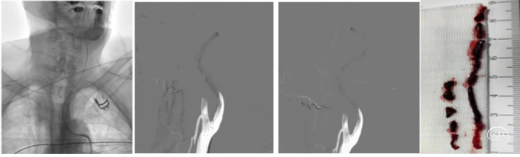

手术方式:全麻,右侧股动脉入路。术中器械8F股动脉鞘、8F90cm 埃普特长鞘、088颅内血栓抽吸导管(8F 115cm)、Rebar18微导管、Synchro-14 2m微导丝。

治疗经过:

通路建立:8F短鞘,交换8F长鞘、5F多功能导管行脑血管。造影示:左侧颈总动脉闭塞,右侧颈内动脉-前交通动脉向左侧大脑中动脉部分代偿供血;左侧大脑中动脉下干闭塞。

8F长鞘引至左侧颈总动脉,088颅内血栓抽吸导管至颈总动脉-颈内动脉C4段抽吸出大量暗红色血栓。

抽吸后造影示:左侧颈总动脉复通,未见明显血栓逃逸;左侧大脑中动脉下干闭塞同术前。

微导管超选至下干近心端推注5ml替罗非班,后造影示下干部分再通,颈内动脉造影示左侧颈内动脉-大脑中动脉复通,eTICI 3级。

撤出导管系统:置入泥鳅,撤出8F长鞘,交换血管闭合系统进行穿刺部位闭合,加压包扎,技术手术。

术后情况:术后第二天复查CTA提示:未见明显出血,左侧颈总动脉-大脑中动脉通畅。患者术后5天转科至康复科,术后1月NIHSS 5分,可独立行走.

2、手术难点是血栓负荷量大,既往常规使用的8F导引导管/6F长鞘配合6F抽吸导管系统可能存在堵管等问题,抽吸效率较低。

3、术中采用8F长鞘进行较强的支撑,使088颅内血栓抽吸导管进行血栓抽吸,大内腔具有更高效的抽吸效果,较短的手术时间也是患者获益的重要因素。